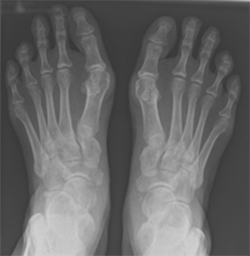

A bunion is a bony prominence at the base of the big toe and usually associated with deviation of the big toe (hallux) in an outward direction (valgus) - hallux valgus.

Image of x-ray showing feet with bunion  Image of x-ray showing feet with bunion corrected using screw fixation